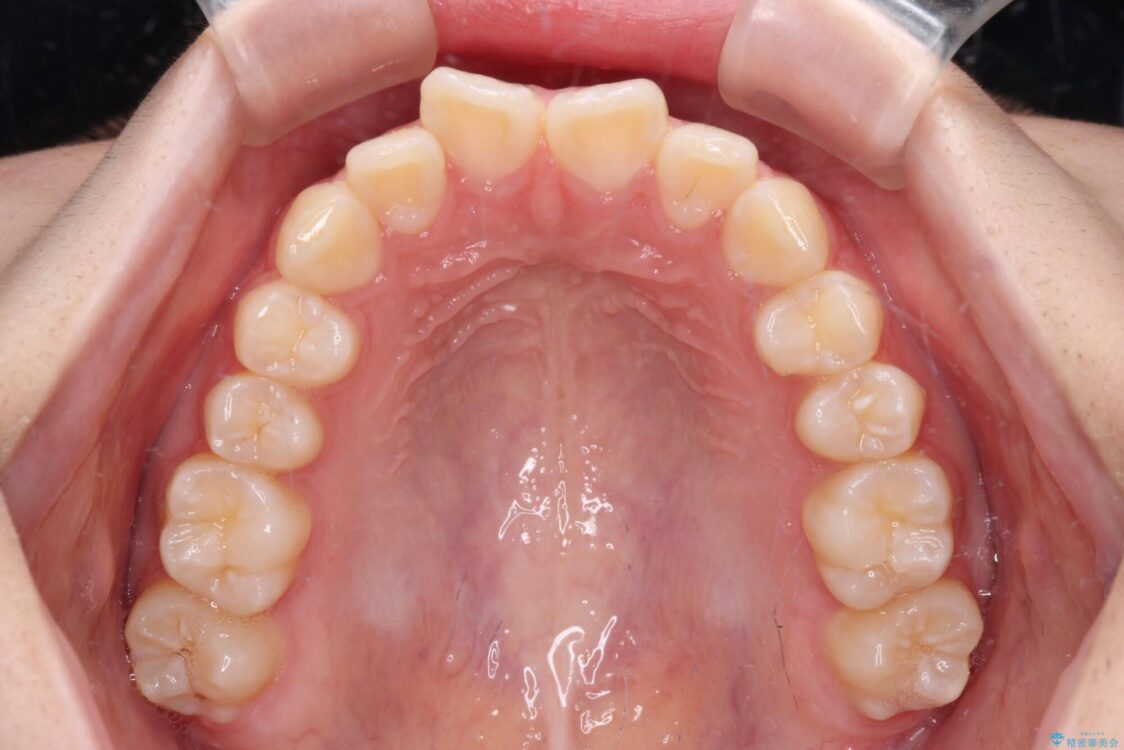

上下前歯のねじれを気にして来院された患者様です。

ワイヤー矯正でもマウスピース矯正でも対応可能でしたが、マウスピース矯正の自己管理が面倒であること、上顎前歯の捻転が著しいことから、ワイヤー矯正での治療を希望されました。

治療前

• インビザラインは使える自信がない ワイヤー装置にて矯正治療 治療前画像